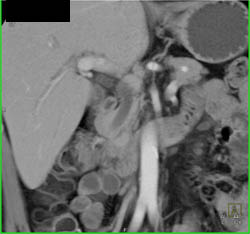

Subtle Tumor of the Body of the Pancreas